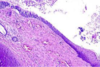

What is this showing in the lungs and why?

Pulmonary TB

Early Mycobacterium tuberculosus - early caseous granuloma , central area of caseous necrosis (CN), surrounded by macrophages (M) which fuse to giant Langerhans cells (L). Arrows = rim of lymphocytes.